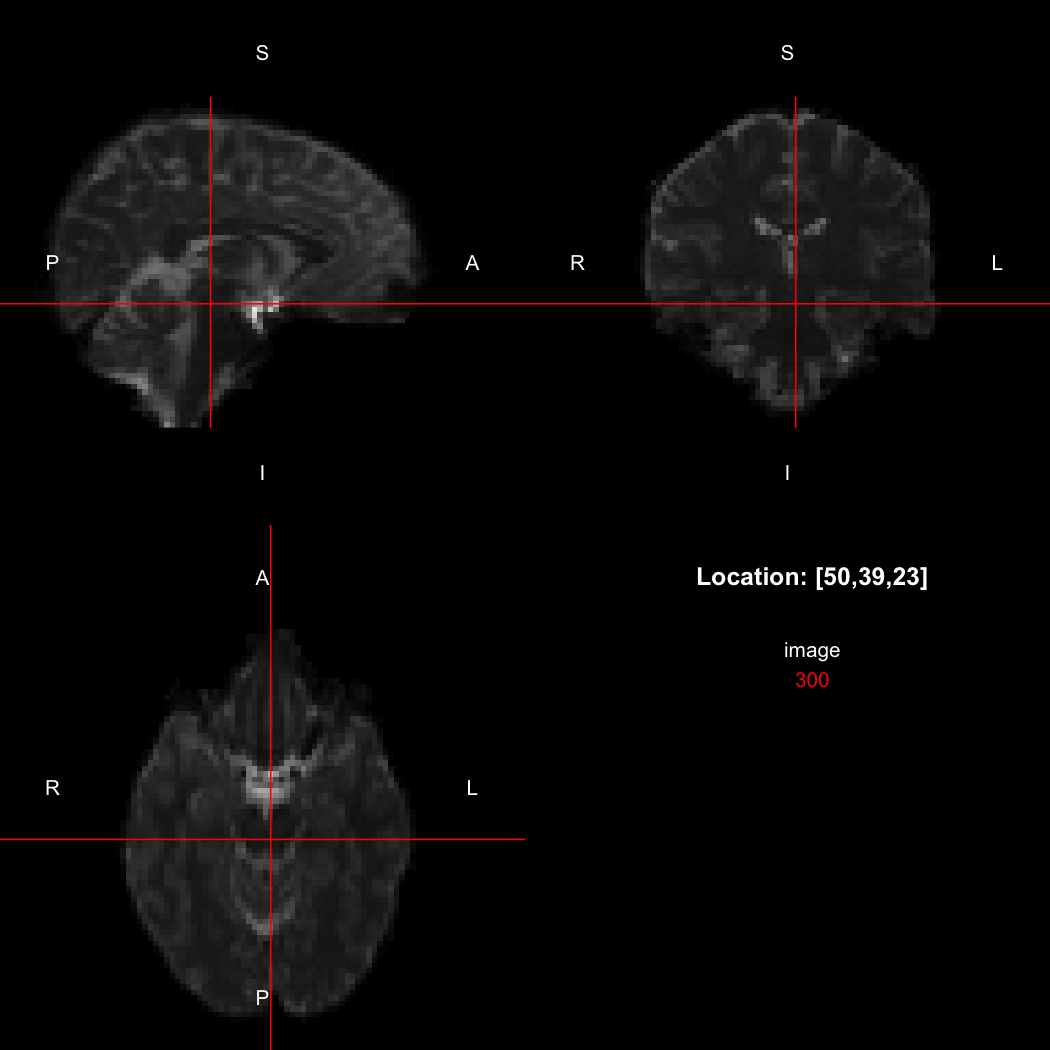

So, here, “LAS” means that the positive x-axis points left, the positive y-axis anterior and the positive z-axis superior. This is the so-called “radiological” orientation convention, and can be requested when viewing images for those who are used to it:

view(image, radiological=TRUE)

plot of chunk unnamed-chunk-12

Notice the left (L) and right (R) labels, relative to the view shown above. Setting the radiologicalView option to TRUE will make this the default for all future views.

There is a replacement version of the orientation function, which will reorient the image to align with the requested directions. This is a relatively complex operation, affecting the xform and the storage order of the data.

image[50,39,23]

## [1] 300

orientation(image) <- "RAS"

## [1] 310

image[47,39,23]

Notice that the sign of the top-left element of the xform has now flipped, and the value of the image at location (50,39,23) has changed because the data has been reordered. The equivalent x-location is now 47, which is the 50th element counting in the other direction (96 - 50 + 1 = 47).